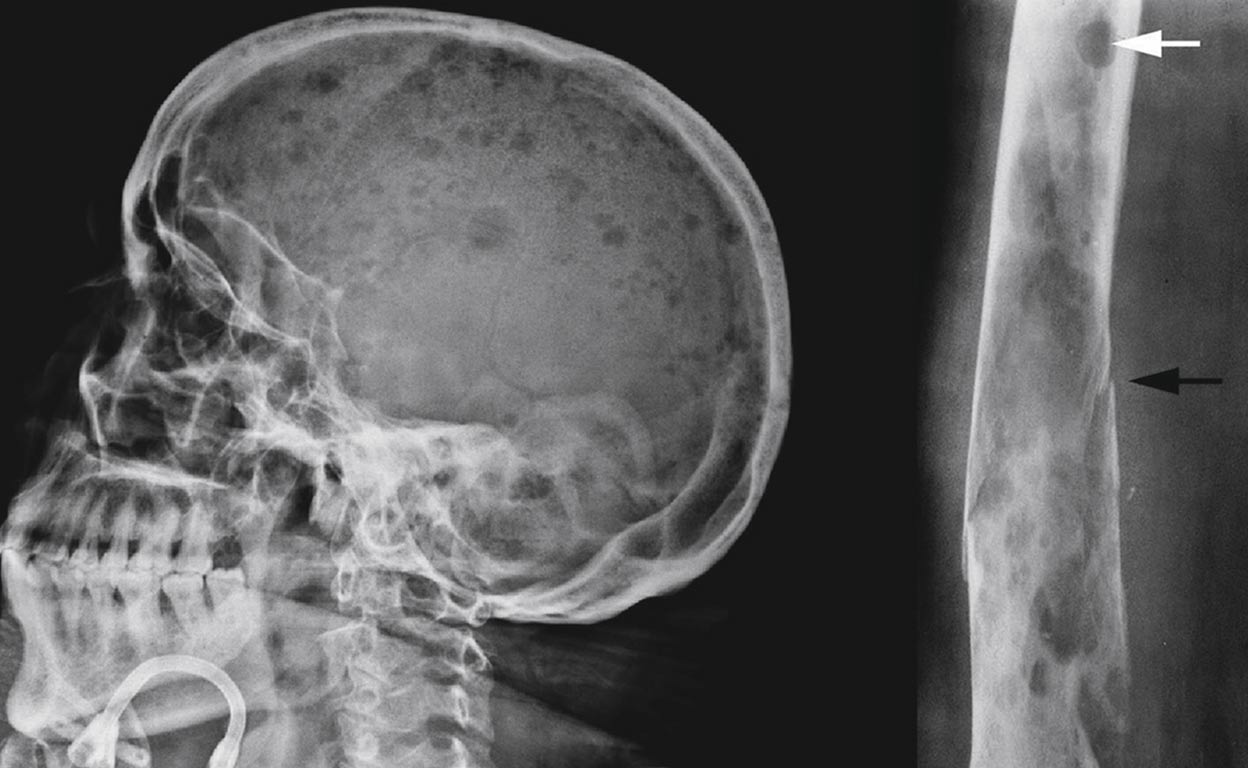

Agujeros en el cuerpo. Cráneo y fémur de enfermos de mieloma, con 'agujeros' causados por el cáncer. La enfermedad deteriora los huesos por el mal funcionamiento de las células plasmáticas de la médula.

El mieloma es un cáncer de la médula ósea que acaba ‘comiéndose’ los huesos. Es difícil de diagnosticar.

La enfermedad deteriora los huesos por el mal funcionamiento de las células plasmáticas de la médula